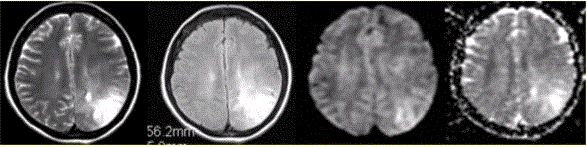

女性,42岁。癫痫1个月,近期加重。无发热,无其他病史。MRI表现如下图。为进一步确诊,MRI增强检查及MRS(Cho升高)结果如下图。可能的诊断...

问题 女性,42岁。癫痫1个月,近期加重。无发热,无其他病史。MRI表现如下图。 为进一步确诊,MRI增强检查及MRS(Cho升高)结果如下图。可能的诊断为

选项 A.脑脓肿 B.转移瘤 C.星形细胞瘤 D.结核瘤 E.脑膜炎

答案 C